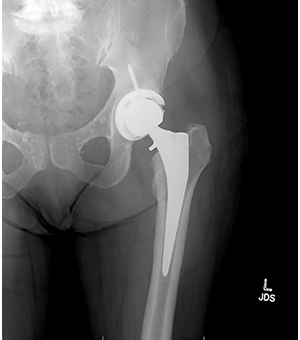

Cynthia’s daughter works in the health care field and encouraged her to get an X-ray of her hip. The imaging revealed severe arthritis with bone-on-bone grinding caused by the wearing away of the cartilage in her hip joint. Cynthia also had bone spurs, which commonly develop when the cartilage “cushioning” wears away.

She needed a total replacement of the left hip.

During the surgery, Shields accessed Cynthia’s hip joint from the back of the leg, which is known as a minimally invasive posterior approach. It is traditionally the most common way to perform a hip replacement, in which damaged sections of the hip are replaced with artificial ball and socket components.